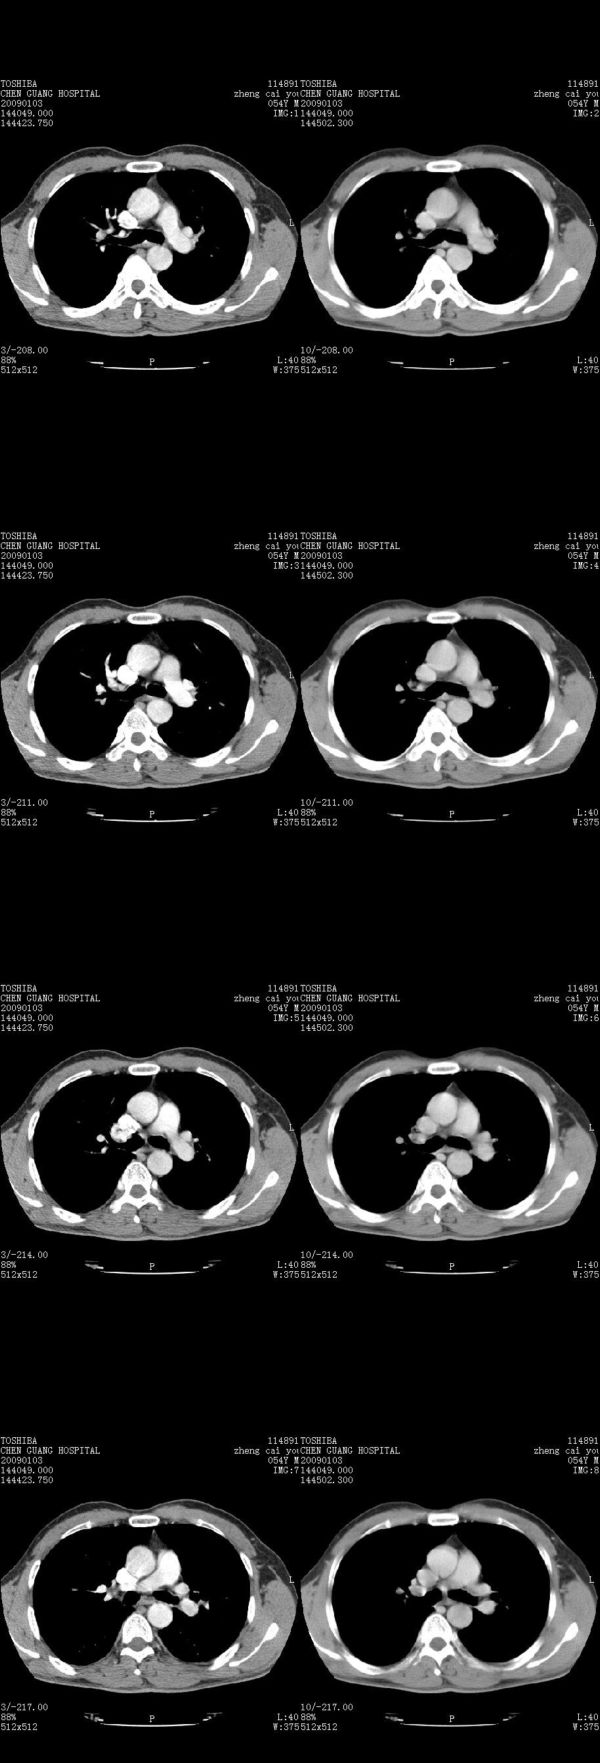

男,54岁,右侧胸部疼痛,平时吸烟,有抽烟后咳嗽咯痰史。昨天没把xiphoid软件吃懂,所以没把纵隔窗图像处理出来!请各位老师帮忙看一下右肺门有没有问题?谢谢!!!!!!!!!!

我同学讲红线部分强化不好,感觉不是很舒服,这是什么道理?

我同学讲红线部分强化不好,感觉不是很舒服,应该 是软组织间隙,不是一个孤立的病灶。

气管前腔静脉后似见增大淋巴结影,肺门区未见明显肿块影。肺窗示右肺中叶外侧段透亮度增高,可过一段时间再查一下对比一下,毕竟是自己的至亲,又有条件,辐射就顾不得了。

也觉得还好吧,只是右下肺动脉显粗了点,纵膈有钙化淋巴结,再有肺窗就更好了

各位老师:奇静脉增宽,肺上未见明显实变,这还需注意观察些什么?????

右侧肺门影增大,不除外增大淋巴结可能